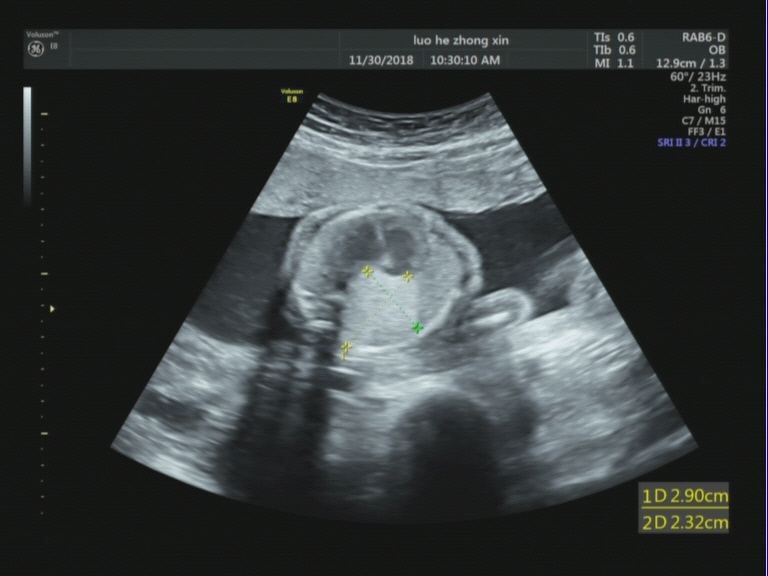

胎儿右肺可见范围约29mmx23mm的稍强回声。

【超声图像】

胎儿右肺稍强回声(考虑1.囊腺瘤? 2.隔离肺不除外)